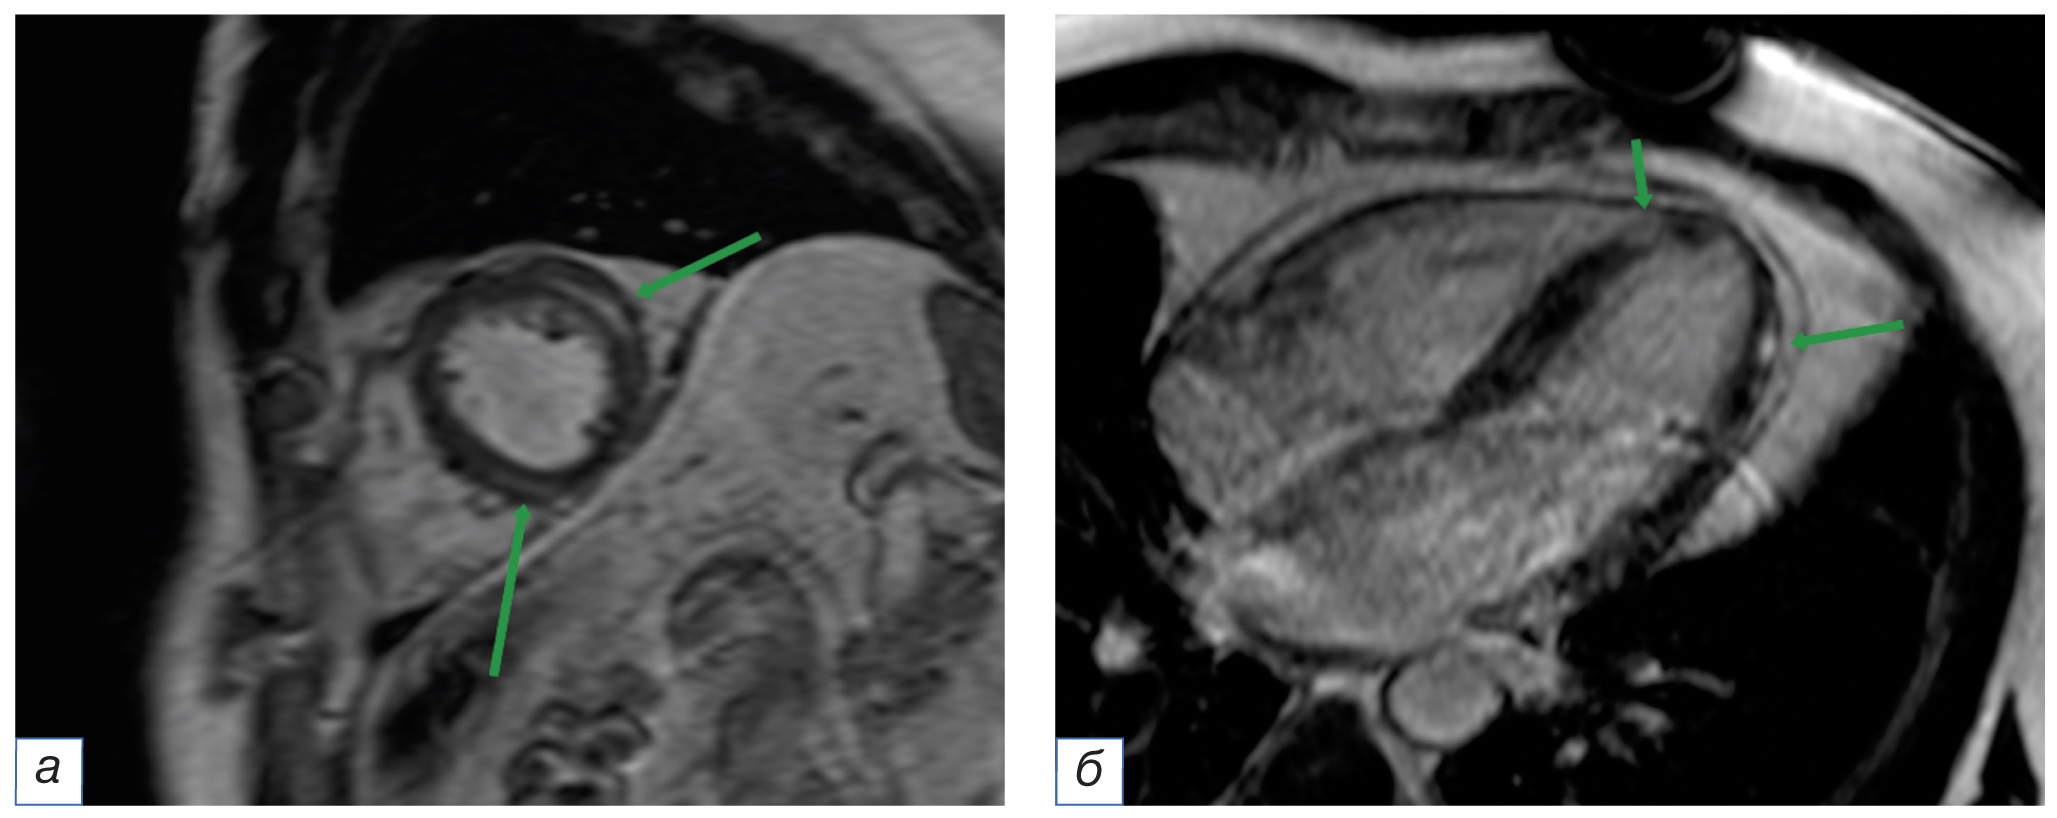

В результате длительного воспаления происходит повреждение миоцитов, приводящее к некрозу тканей и дальнейшему формированию фиброза. Для оценки миокарда на наличие участков рубцовых изменений используют последовательности инверсия–восстановление, в которых с помощью инверсионного импульса уменьшается сигнал от неповреждённого миокарда и выделяются области с повышенным накоплением контрастного препарата в виде ярких участков, соответствующих фиброзу и воспалению (рис. 3) [25]. Полученные в результате отсроченного контрастирования изображения очень важны для пациентов с клиническим подозрением на миокардит и демонстрируют характерные неишемические паттерны [26, 27].

Рис. 3. Магнитно-резонансная томография сердца, отсроченные серии с контрастным усилением (MDE): а — изображение по короткой оси сердца; б — четырёхкамерная проекция. Стрелками указаны интрамиокардиальные очаги накопления контрастного препарата, соответствующие воспалению.

Fig. 3. Cardiac magnetic resonance imaging, myocardium delayed enhancement series (MDE): а — short axis plane; б — 4-chamber plane. The arrows indicate intramyocardial foci of the contrast enhancement, corresponding to inflammation.

Для хорошей дифференцировки здоровой и поражённой ткани важен правильный выбор времени инверсии (inversion time, TI), которое обеспечивает однородный низкоинтенсивный сигнал от миокарда и оптимальную контрастность между кровью и миокардом. Подбор TI осуществляется с помощью последовательности TI-scout, которая получает срезы по короткой оси на одном уровне с разными значениями TI.

При введении одномолярного контрастного вещества в расчёте 0,2 мл на 1 кг веса в интервале от 10 до 20 минут сохраняется оптимальная контрастность между здоровым и повреждённым миокардом. Микроскопические [28], животные [29] и клинические [30] исследования подтвердили роль отсроченного контрастирования в качестве золотого стандарта визуализации повреждения сердечной мышцы при миокардите. У пациентов с верифицированным миокардитом отсроченное контрастирование продемонстрировало высокую чувствительность выявления повреждения миокарда [31–33].